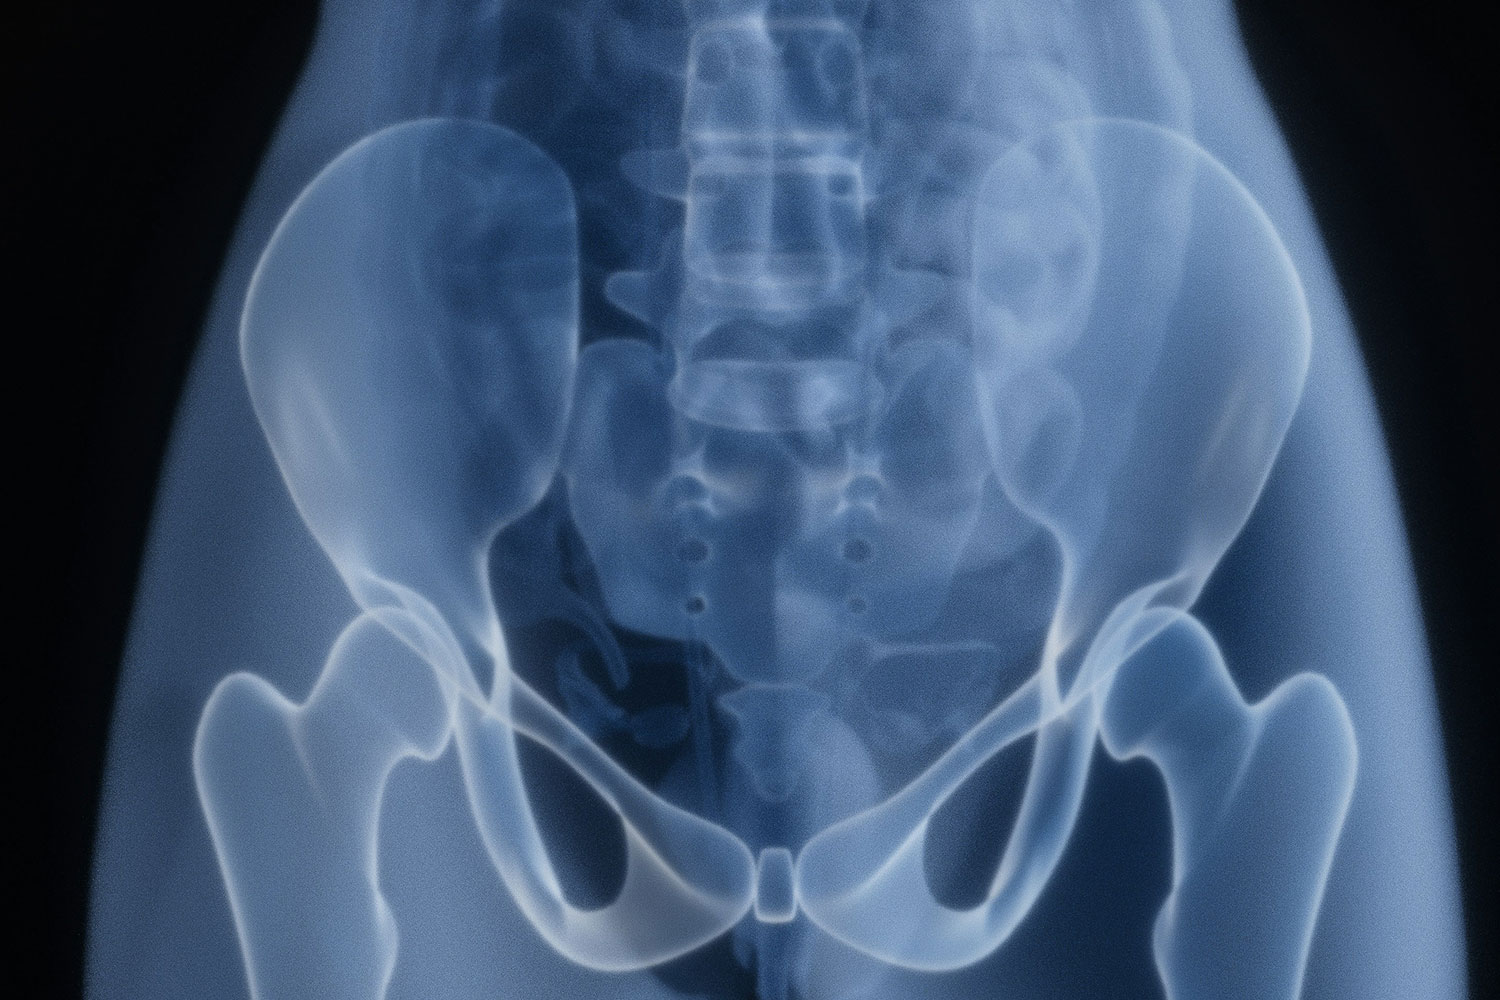

Additionally, the Foundation purchased an anthropomorphic phantom — a 180-pound male skeleton with tissue density to match a live human. State law does not allow for live imaging practice, so students rely on the phantom to learn the tactile skills.